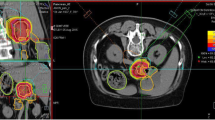

Evaluated plans for pancreatic adenocarcinoma (A) and for glioblastoma (B) patient cases are displayed in Fig. 1. The prescription dose and target optimization goals were achieved as shown in biological dose maps and the dose volume histograms (DVHs) outlined in panels (D). LETd maps, LETd profiles and LETd-volume histograms (LVHs) demonstrate that the maximum LETd for IMPT plans is placed outside of the target volume and extends into normal tissues. For the GTV, LETd values were around ∼40–65 keV/µm. In order to increase LETd in the target, LETd optimization feature was also investigated in Fig. 1 (IMPTLET). As observed from the LETd distribution, the inclusion of LETd-boosting allows LETd-escalation at the GTV, while having a minimum impact on the target dose coverage (see DVH for the clinical target volume, CTV). IMPTLET allowed an increase in the GTV minimum LETd from 55.1 keV/µm to 87.1 keV/µm, and from 38.4 to 48.6 keV/µm, for the glioblastoma and pancreatic adenocarcinoma cases, respectively. However, LETd optimization comes at the expense of an increase in the beam’s entrance biological dose. For the glioblastoma patient, for example, there could be an increase of up to 30% in the biological dose delivered to the skin directly exposed to the entrance channel. Additionally, for IMPTLET plans, normal tissue DVH highlights an increase of the volume in the middle range doses (20–30 Gy (RBE)) compared to standard IMPT.

Simultaneously, the LETd escalation is still constrained by the chosen beam arrangement. In scenarios in which two posterior beams are used, as seen in pancreatic cases currently treated at HIT, although IMPTLET raises LETd in the GTV, the high-LETd region is still focused at the distal edge of the tumour volume.

For both glioblastoma and pancreatic cases shown in Fig. 1, SHArc led to an enhancement of the maximum LETd in the GTV up to at least 125 keV/µm, while the minimum GTV LETd values were 46.1 keV/µm and 47.2 keV/µm, respectively. The plotted LETd profiles further demonstrate that the maximum LETd for SHArc plans is concentrated in the central region of the tumour.

Maps of biological dose (DRBE) and LETd for IMPT, IMPTLET and SHArc plans for (A) pancreatic adenocarcinoma and (B) glioblastoma patient cases using carbon ions. For visualisation, the LETd values are displayed with a 5 and 20 Gy low-dose threshold, for glioblastoma and pancreatic cases, respectively. The white lines in the LETd map designate the LETd profiles presented in panel (C). (C) Profiles for LETd are presented highlighting the LETd range within the GTV for both cases. (D) DRBE- and LETd-volume histograms are shown for relevant organs of interest, for the IMPT (full line), IMPTLET (dashed line) and SHArc plans (dotted line). For the DVH plots (top row), the CTV is shown (orange), as well as either the body excluding the PTV or the brain excluding PTV (pink), for the pancreatic and the head case, respectively. In the LVH plots (bottom row), the GTV is shown for both cases (green), as well as the main OAR for each case (red): the gastrointestinal tract for the pancreatic adenocarcinoma and the ventricles of the brain for the case of the glioblastoma. For the pancreatic case, two lines are mostly indistinguishable for the OAR shown in both the DVH and the LVH, due to the nearly overlap between IMPT and IMPTLET volume histograms (i.e., full and dashed lines).

This comes at the cost of a low dose-bath as shown in the normal tissue DVHs. In terms of LETd in the OARs, SHArc could be particularly beneficial for pancreatic adenocarcinoma. In this case, the clinical beam arrangement results in higher LETd values towards the beam’s distal edge, thus directly leading to high LETd in the gastrointestinal tract, which is posterior to the tumour. With SHArc shifting the high LETd towards the tumour’s centre, there is a direct reduction of the near-maximum LETd in the gastrointestinal tract. Specifically, SHArc lowers the maximum LETd in the gastrointestinal tract to 47.5 keV/µm compared to 88.0 keV/µm and 83.0 keV/µm found for the IMPT and IMPTLET plans, respectively. For the glioblastoma case, in which opposite fields are considered as the standard, the reduction of the near maximum LETd in the surrounding OAR, i.e., the brain ventricles, is less pronounced. Nonetheless, there is still an observed decrease in the LETd5%, from 88.4 keV/µm to 79.7 keV/µm.